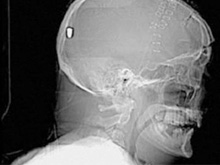

В Британии врачи нашли у пациента пулю в голове13.05.10 13:07 Прочтений новости 1461 Общество В Британии у пациента, который поступил в клинику с подозрением на инсульт, врачи обнаружили пулю в голове. Но остается неизвестным, как мужчина получил ранение.Рентгеновские снимки головы показали, что в полости черепа находится инородный предмет. Мужчине сделали томографию головы, и врачи установили, что этим предметом является пуля. Как сообщается, 19 апреля 61-летний Питер Хесфорд упал во время работы у себя в саду. Позже его обнаружила жена, которая вызвала скорую. Мужчина оставался в сознании, но не мог говорить. Медики, прибывшие на место, заподозрили у Питера Хесфорда инсульт и доставили его в Больницу Уитеншо. Эксперты по баллистике, изучив снимки пациента, пришли к выводу, что пуля, застрявшая в затылочной области, могла попасть туда через глаз. Но мужчина не помнит, что именно с ним произошло. Врачи попытались удалить пулю, однако это оказалось невозможным из-за ее положения по отношению к окружающим структурам. Пациент остается в больнице, а его состояние расценивается как стабильное. Комментарии (всего 0)